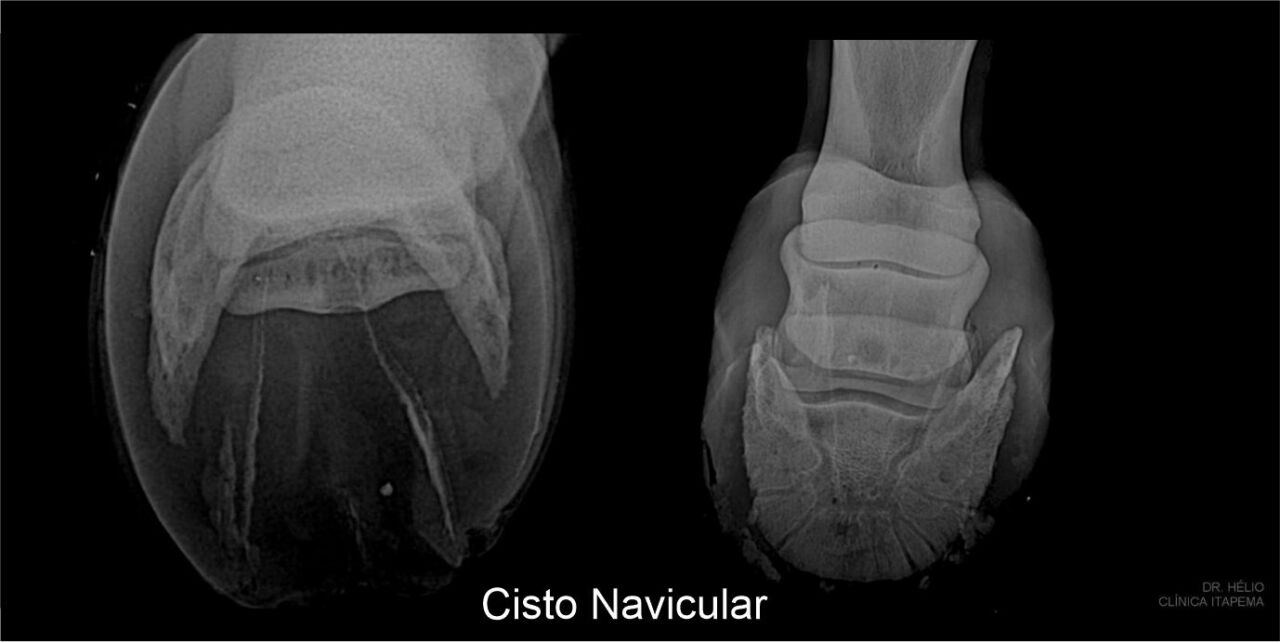

Como fazer o diagnóstico da síndrome do navicular

O diagnóstico da síndrome do navicular comumente é feito através do histórico e sinais clínicos, na resposta ao bloqueio anestésico dos nervos digitais palmares e nas alterações encontradas nos exames de imagem. O aprimoramento no diagnóstico precoce das lesões que causam claudicação tem levado os médicos veterinários e ferradores a uma intervenção com melhores resultados para o tratamento e diminuição da velocidade de progressão da doença.

Imagem de exames: arquivo de Hélio Itapema